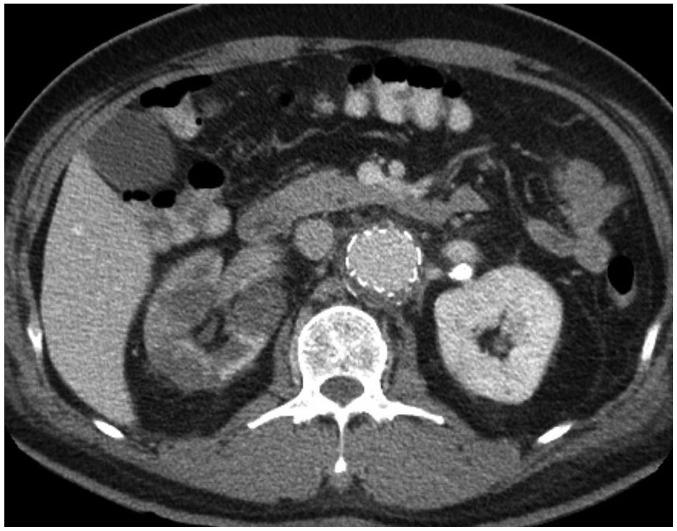

Abdominal aortic aneurysm (AAA) can be defined as an abnormal, progressive dilatation of the abdominal aorta, carrying a substantial risk for fatal aneurysmal rupture. Endovascular aneurysmal repair (EVAR) for AAA is a minimally invasive endovascular procedure that involves the placement of a bifurcated or tubular stent-graft over the AAA to exclude the aneurysm from arterial circulation. In contrast to open surgical repair, EVAR only requires a stab incision, shorter procedure time, and early recovery. Although EVAR seems to be an attractive solution with many advantages for AAA repair, there are detailed requirements and many important aspects should be understood before the procedure. In this comprehensive review, fundamental information regarding AAA and EVAR is presented.

腹主动脉瘤(AAA)可定义为一种腹部主动脉的异常、进行性扩张,具有致命性的动脉瘤破裂的巨大风险。AAA 的血管内修复术(EVAR)是一种微创的血管内手术,涉及在 AAA 上方放置分叉或管状支架移植物,将动脉瘤从动脉循环中排除。与开放手术修复相比,EVAR 仅需要一个刺切口、更短的手术时间和更早的恢复。尽管 EVAR 对于 AAA 修复似乎是一种具有许多优势的有吸引力的解决方案,但在进行该手术之前,需要了解详细的要求和许多重要方面。在本全面综述中,介绍了关于 AAA 和 EVAR 的基本信息。